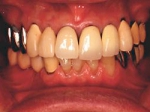

両側5歯症例

両側5歯症例両側5歯症例両側5歯症例 主訴-義歯のバネが壊れて手前の歯が痛んできた。 術前(旧義歯装着、鏡像) 術前(下顎粘膜面、鏡像)術前(下顎粘膜面、鏡像)術前(下顎粘膜面、鏡像) 術前レントゲン術前レントゲン術前レントゲン 術前口腔内(正面観)術前口腔内(正面観)術前口腔内(正面観)

術後(鏡像)術後(鏡像)術後(鏡像) 術後口腔内(正面観)術後口腔内(正面観)術後口腔内(正面観)もう入れ歯は要らなくなりました。 術後レントゲン術後レントゲン術後レントゲン